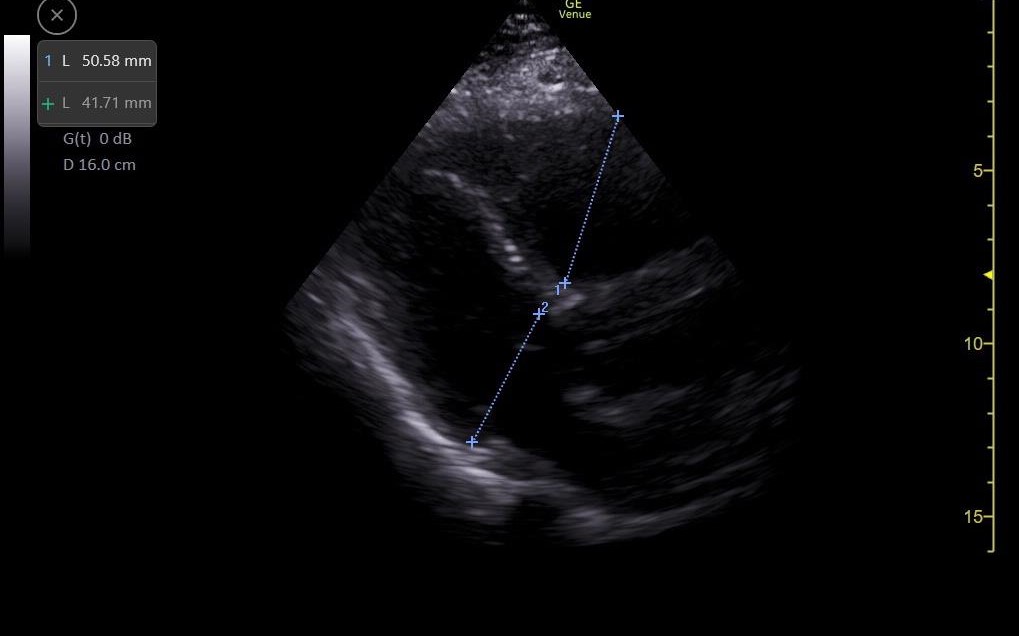

Se realiza ecografía clínica de vasos en miembros inferiores objetivándose un trombo en vena poplítea derecha y ecocardioscopia con dilatación de ventrículo derecho.

Solicitamos electrocardiograma donde se objetiva taquicardia sinusal a 105 lpm y ondas T negativas en V1 y V2, radiografía de tórax sin alteraciones y analítica sanguínea donde destaca DD 156223. Se completa el estudio realizándose angioTC de arterias pulmonares que es informado como tromboembolismo pulmonar bilateral con afectación de todas las ramas lobares bilaterales con imagen compatible con infarto pulmonar en lóbulo superior izquierdo y signos de sobrecarga cardíaca derecha.

Tromboembolismo pulmonar con sobrecarga de cavidades derechas.

La ecografía clínica puede ser una herramienta de gran utilidad para el diagnóstico de trombosis venosa profunda, al igual que para poder determinar importantes factores pronósticos de un tromboembolismo pulmonar, como en este caso la sobrecarga de cavidades derechas, permitiendo una aproximación diagnóstica de forma rápida antes de realizar pruebas complementarias adicionales.